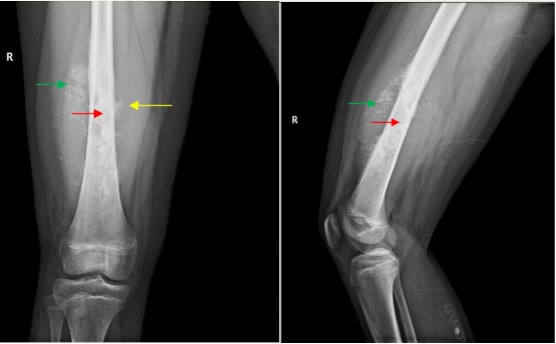

接受右侧股骨X线正侧位摄片发现股骨中下段骨质虫蚀样破坏、放射状骨膜反应和较大软组织肿块等恶性肿瘤征象。

右股骨正侧位摄片可见股骨内虫蚀样破坏和肿瘤骨形成(红箭头),股骨表面放射状骨膜反应(黄箭头)和骨外的软组织肿物(绿箭头)。是恶性骨肿瘤(骨肉瘤)的典型征象